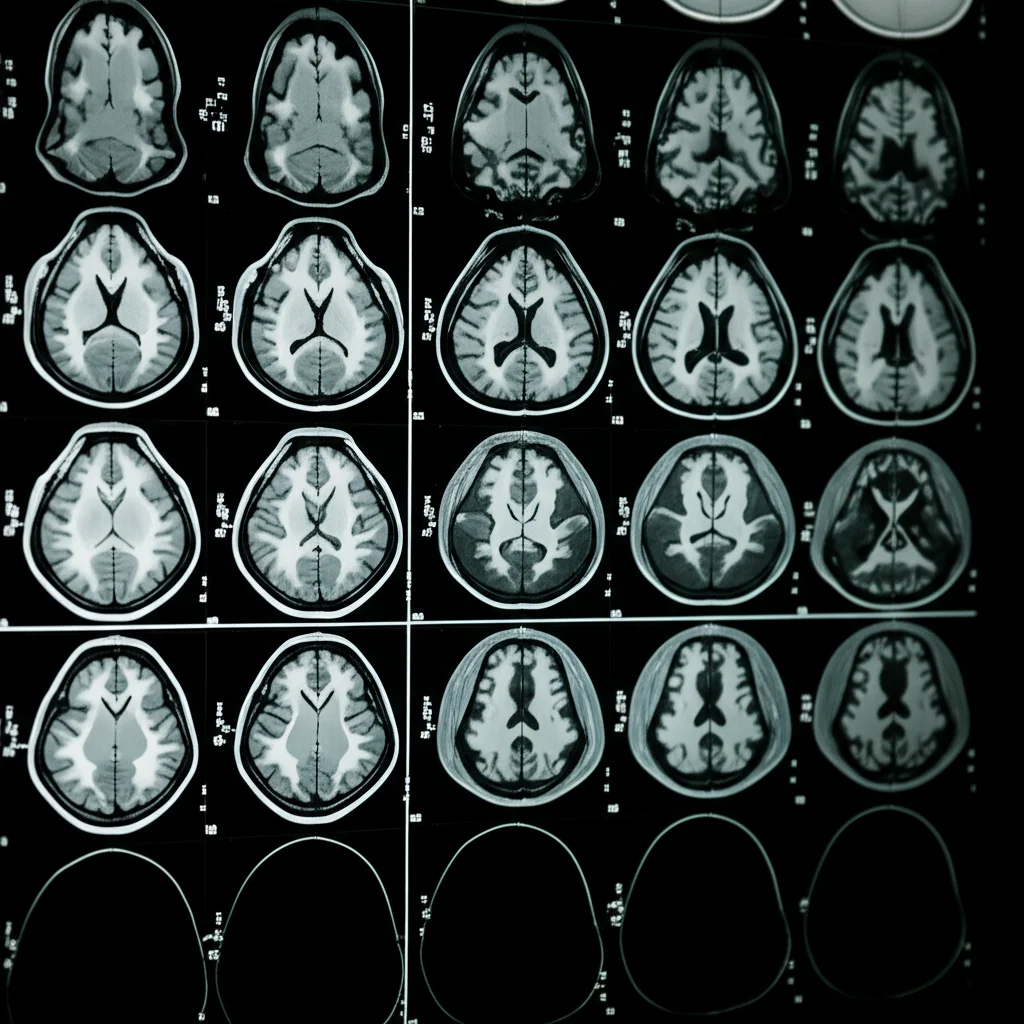

This is where some really cool technology comes into play – specifically, using MRI scans and something called radiomics, powered by artificial intelligence (AI), including deep learning. Think of it like this: MRI scans give us incredibly detailed pictures of the inside of the body. Radiomics is a fancy term for extracting a ton of quantitative data – numbers, patterns, textures – from these images that you can’t necessarily see just by looking. And deep learning? That’s a powerful type of AI that can learn complex patterns from this data.

We focused on two specific types of MRI sequences: contrast-enhanced T1-weighted (T1WI+C) and T2-weighted (T2WI). These sequences highlight different tissue properties and can give us complementary information about the tumor.